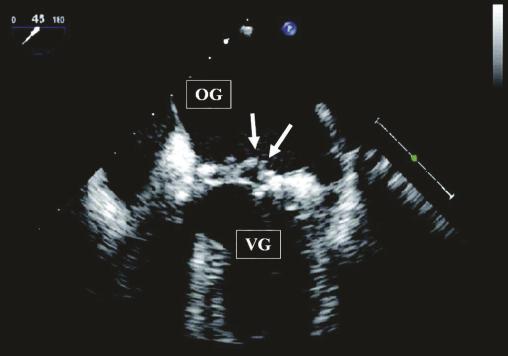

Image échocardiographique par voie transœsophagienne : aspect de végétations (flèches) sur le versant auriculaire de la valve mitrale située entre l’oreillette gauche et le ventricule gauche.